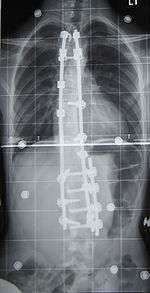

Surgery

Surgery is usually recommended by orthopedists for curves with a high likelihood of progression (i.e., greater than 45 to 50° of magnitude), curves that would be cosmetically unacceptable as an adult, curves in patients with spina bifida and cerebral palsy that interfere with sitting and care, and curves that affect physiological functions such as breathing.

Surgery is indicated by the Society on Scoliosis Orthopaedic and Rehabilitation Treatment (SOSORT) at 45 degrees to 50 degrees[40] and by the Scoliosis Research Society (SRS) at a Cobb angle of 45 degrees.[41] SOSORT uses the 45-degree to 50-degree threshold as a result of the well-documented, plus or minus five degrees measurement error that can occur while measuring Cobb angles.

Surgery for scoliosis is performed by a surgeon specializing in spine surgery. For various reasons, it is usually impossible to completely straighten a scoliotic spine, but in most cases, significant corrections are achieved.

The two main types of surgery are:

- Anterior fusion: This surgical approach is through an incision at the side of the chest wall.

- Posterior fusion: This surgical approach is through an incision on the back and involves the use of metal instrumentation to correct the curve.

One or both of these surgical procedures may be needed. The surgery may be done in one or two stages and, on average, takes four to eight hours.